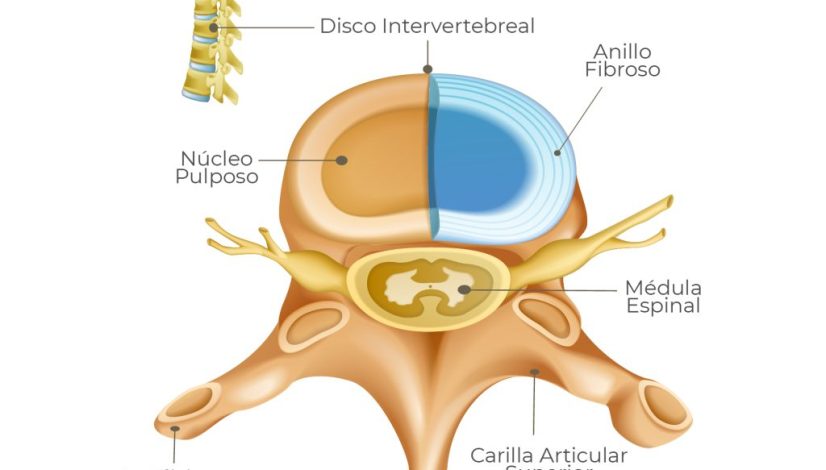

Estructura del disco intervertebral

El disco intervertebral está compuesto por dos partes principales: el núcleo pulposo y el anillo fibroso. El núcleo pulposo es una sustancia gelatinosa que proporciona la capacidad de compresión y amortiguación, mientras que el anillo fibroso rodea y mantiene el núcleo en su lugar, ofreciendo soporte y estabilidad.

Protección de la médula espinal